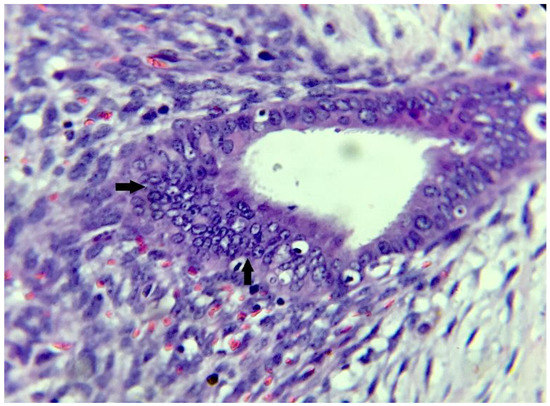

2. Case Presentation